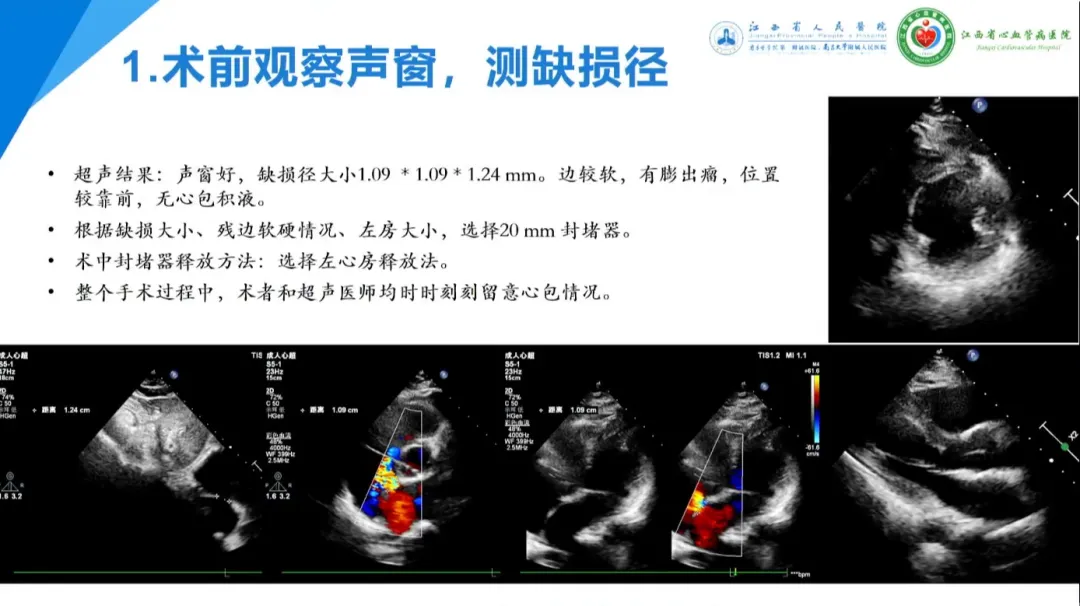

高峰:边缘不良型房间隔缺损一例(19P)